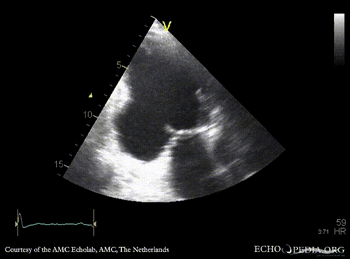

Case 26

Aneurysm of basal inferior wall

Courtesy of: AMC Echolab, AMC, The Netherlands

A2CH: aneurysm of basal inferior wall A3CH: aneurysm of basal inferior wall